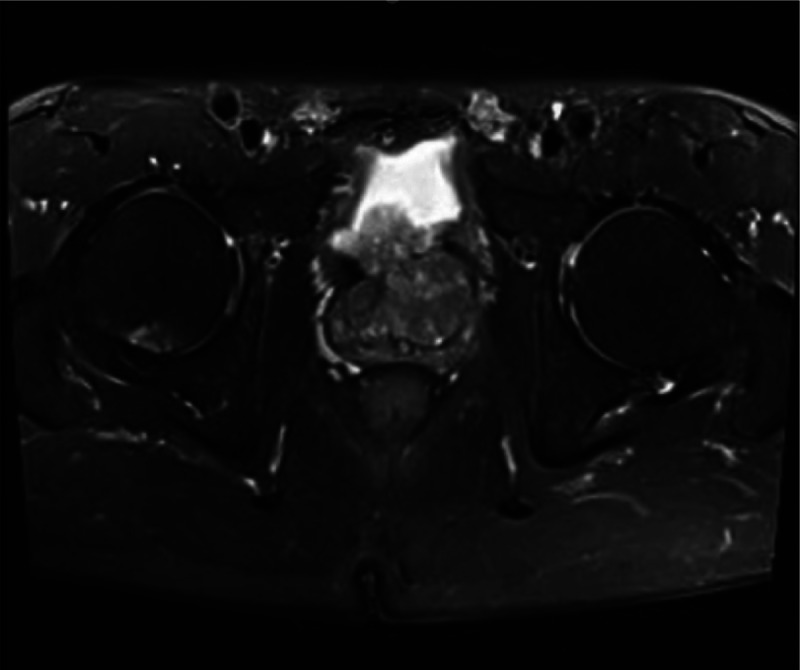

良性前列腺增生常见于老年男性,手术是主要治疗方法。前列腺增生结节,尤其是包埋性包膜增生结节的处理,对于减少术后并发症的发生率和减少重复手术的需要至关重要。我们就前列腺增生结节的来源、结节与前列腺手术包膜的关系、各种手术方式治疗增生结节的优缺点以及手术对术后并发症发生率的影响进行综述。此外,我们也将分享我们使用铥激光切除前列腺内埋包膜增生结节的治疗经验。我们希望医生在临床实践中重视前列腺手术中浸润性囊膜增生结节的处理。

Benign prostatic hyperplasia is commonly observed in older men, and surgery is the primary treatment. Management of prostatic hyperplasia nodules, especially embedded capsular hyperplasia nodules, is crucial for reducing the incidence of postoperative complications and the need for repeat surgery. We summarize the sources of prostatic hyperplasia nodules, relationship between the nodules and the surgical capsule of the prostate, advantages and disadvantages of various surgical procedures for hyperplasia nodules, and impact of surgery on the incidence of postoperative complications. Additionally, we share our experience with the management of embedded capsular hyperplasia nodules using thulium laser enucleation of the prostate. We hope that doctors will pay attention to the management of embedded capsular hyperplasia nodules during prostate surgery in their clinical practice.